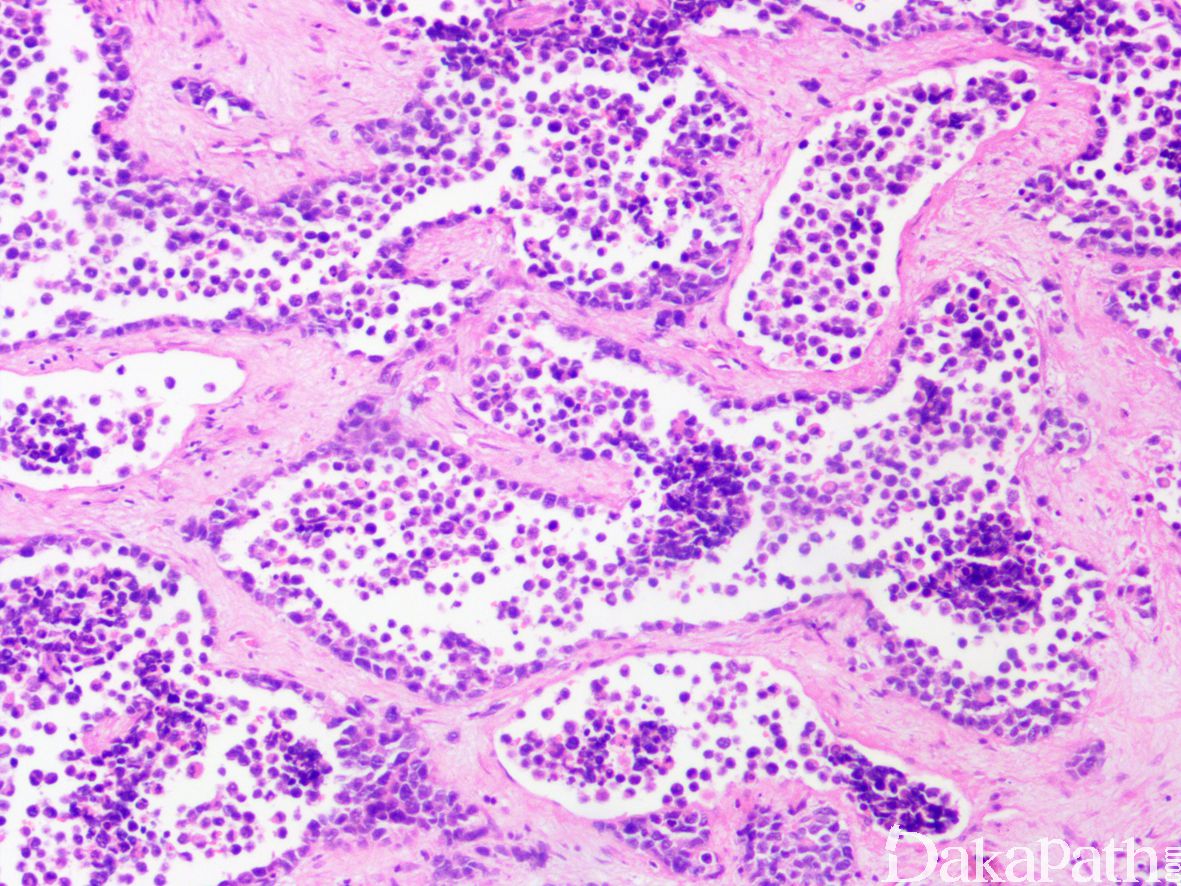

3. 经典型:

4. 瘤细胞排列成片状和巢状而贴附于纤维性间隔上,巢中央瘤细胞黏附性差,相互解离,形成特征性的假腺泡状或微囊状结构;

5. 肿瘤由未分化的原始间叶性细胞及少量早期分化的幼稚横纹肌母细胞组成;

6. 原始间叶性细胞呈圆形、卵圆形或小多边形,胞质少,核深染,核分裂像易见;

7. 腺泡中央的横纹肌母细胞多呈圆形或卵圆形,有时可见到胞质内横纹;

8. 部分病例可见散在的胞质淡染或弱嗜酸性,核位于胞质周边的多核巨细胞;